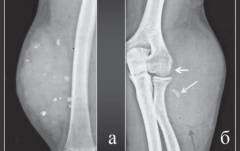

Саркома костей

Саркома костей или саркома Юинга – злокачественная опухоль, чаще всего поражающая бедренные кости (70%) и плечевые кости (14%). Реже затрагивает лопатки, ребра, ключицы, позвонки и кости таза. Это агрессивное новообразование быстро метастазирует. Заболевание чаще встречается у подростков 10-15 лет, причем мальчики страдают в 50% случаев чаще, чем девочки.

Признаки саркомы костей, выявляемые при инструментальном исследовании

- Рентгенография:

- участки разрушения кости выглядят как «изъеденные молью»

- воспаление проявляется «луковичным периоститом»

- нечеткие контуры верхнего слоя кости из-за разволокнения

- выросты на поверхности кости имеют игольчатую или параллельную форму

- значительное повреждение мягких тканей без обызвествления